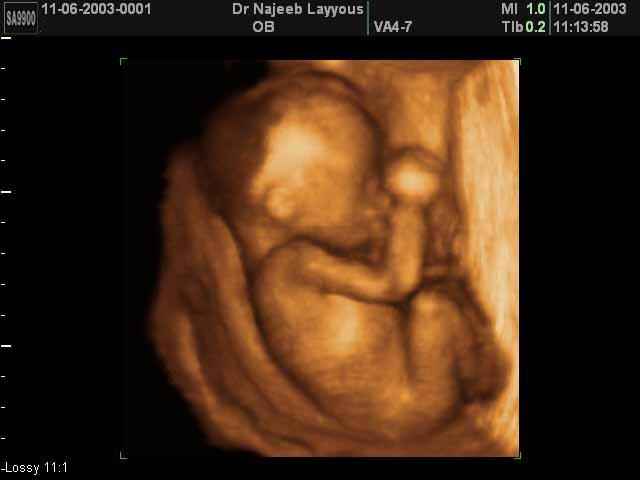

7. haftada embriyonun baş-popo mesafesi (CRL) 6 mm den 11 mm’ye büyür. Gelişmenin bu fazında beyin hızlı geliştiğinden baş vucudun diğer kısımlarına göre daha büyük görülür.

Bebeğiniz süratle büyümeye devam etmektedir. Embrio 14 mmden 21 mm uzunluğa ulaşır. Baş halen büyük ve belirgin yapıdadır ve kalp çıkıntısının üzerine kıvrılmıştır. Yolc kesesi giderek küçülür.

Fetus artık hem vaginal hemde abdominal( karın) ultrasonografi ile rahatlıkla değerlendirilebilir. Baş-popo uzunluğu yaklaşık 2 ila 3 cm’dir. Embrio insan şeklini kazanmıştır. Ultrasonda baş, gövde ve ekstremiteler saptanabilir. Bebeğin kol-bacak ve vücut hareketleri ultrasonda görülebilir. Fetus ekstremitelerini ve gövdesini kımıldatmaya başlar ve rahim içinde takla atarken görülebilir. Ancak anne bunu hissedemez. Cinsiyeti görebilmek mümkün değildir.